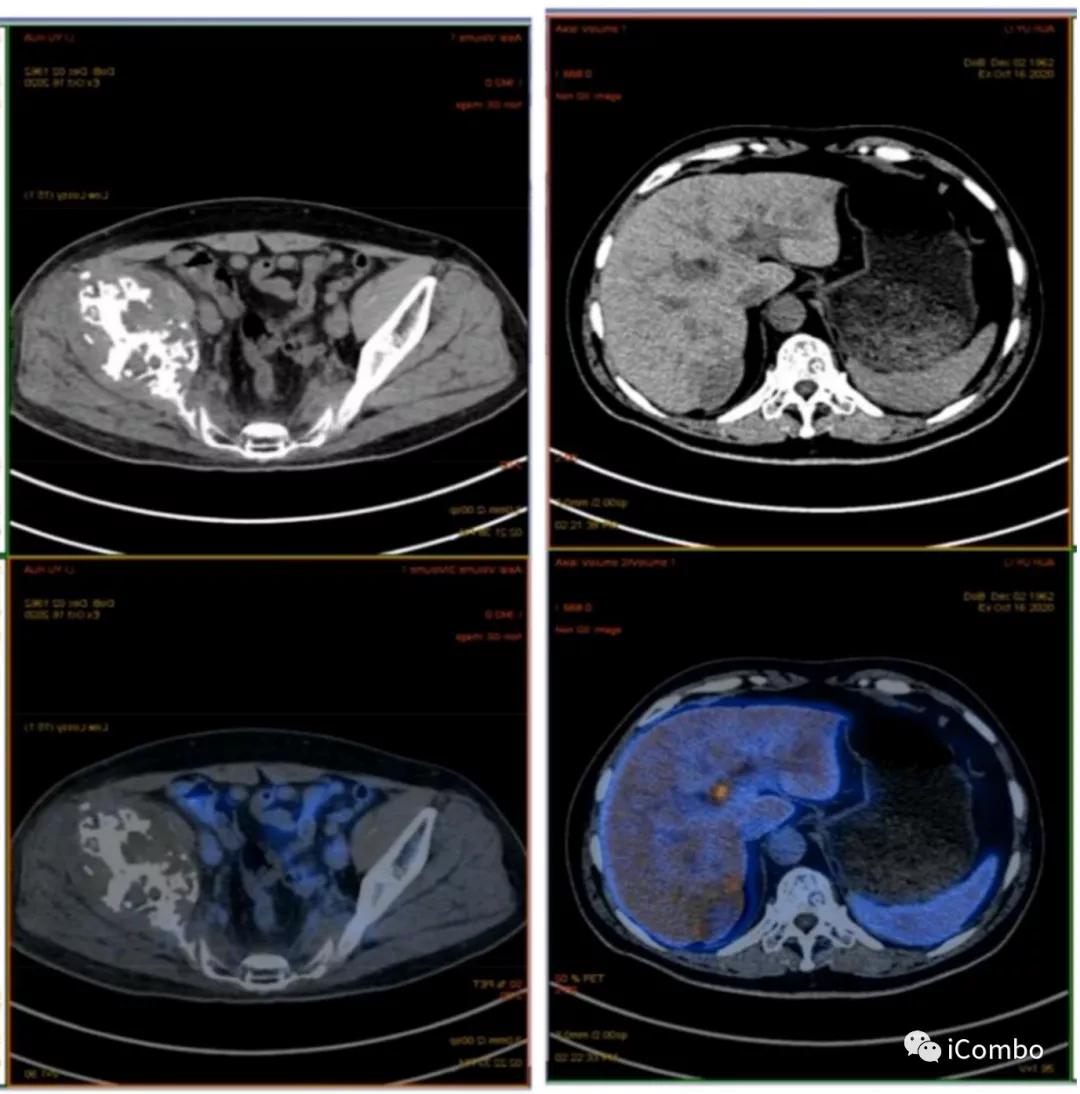

现病史:2012年行左肾癌根治术(肿瘤最大径7厘米),2018-9左髂部疼痛不适,考虑转移瘤,行索坦治疗。2019-06发现左胫骨肿块。2019-7-18 CT示肿瘤较前进展(107*84mm)。

2018.9左髂骨疼痛,穿刺确诊左髂骨转移

2019.6 肿瘤进展,骨痛加剧

3. 肝脏转移

3、2019-10-21:10-8复查MRI:左侧髂骨、坐骨、耻骨骨质破坏,并软组织肿物行程,考虑转移瘤,较前缩小。肝S6/7小片状异常信号影,较前相仿。10-30,施行肝肿物的栓塞消融联合肝动脉注射PD1。治疗两次后复查,肝肿物得到了有效控制,肿物没有继续增大,原来的病灶也出现了液化坏死。

2019-10-8复查:肿物较前缩小

2020-1-8 较11-22肿物较前增大